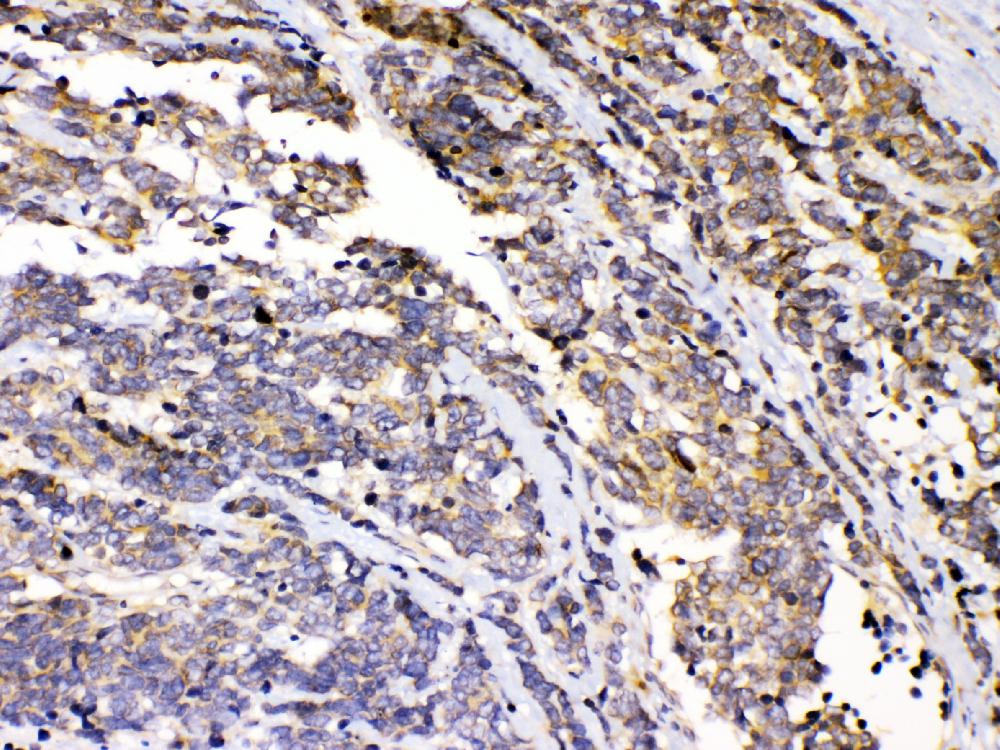

IHC analysis of PRKAR1A using anti-PRKAR1A antibody (A00699-1).

PRKAR1A was detected in a paraffin-embedded section of human intestinal cancer tissue. Biotinylated goat anti-rabbit IgG was used as secondary antibody. The tissue section was incubated with rabbit anti-PRKAR1A Antibody (A00699-1) at a dilution of 1:200 and developed using Strepavidin-Biotin-Complex (SABC) (Catalog # SA1022) with DAB (Catalog # AR1027) as the chromogen.